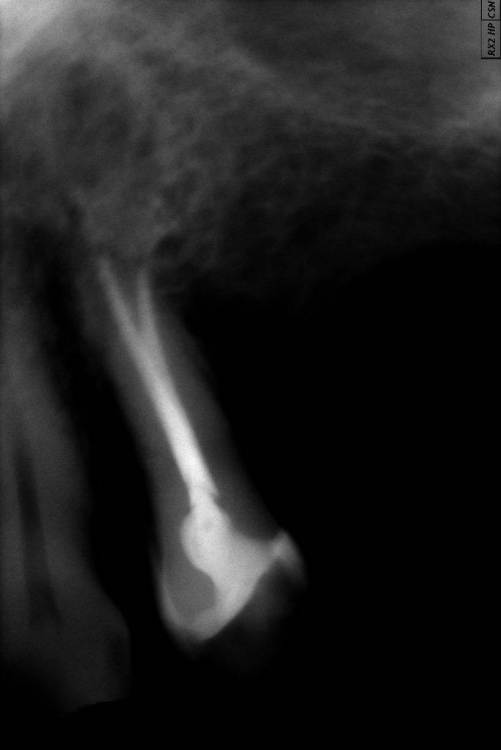

GENRY Опубликовано 6 сентября, 2021 Поделиться Опубликовано 6 сентября, 2021 Здравствуйте! Как лучше восстановить ( пусть частично) 28 зуб? Удаление не желательно т.к. с имплантацией связываться не хочу (синус лифтинг.. возраст 75 лет...) ,а опор для ортопедических конструкций нет. Кроме того боюсь, что в процессе удаления будет разрушена пломба 27 _го. Оптимизма добавляет история 27 го На орто 2012г показан 27 до его восстановления и до вмешательства в 28 зуб с добавлением в него пломбы в 2012г . Канал 28_го (небный ?) был уже запломбирован кем то раньше, скорее всего резорцин-формалиновой пастой) Доктор в 27 - м обнаружил на снимках 3 канала, наполовину прошел небный и полностью прошел дистально- щечный канал с наполнением их горячей гуттаперчей . Поскольку устье 3_го канала обнаружено не было, восстановил 27 зуб 2_мя стекловолоконными штифтами с использованием Build-It . Дистальную стенку сделал, кажется на основе пасты СПЕКТРУМ . К дальнейшей судьбе 27_го доктор отнесся скептически ( не более 2_х лет!), но похоже сработал надежно, пошел уже 10_й год, а 27 все стоит. Но 10 мес. назад выпала пломба 28 _го и он принял вид показанный на снимке. Не беспокоит. Хотелось бы повторить историю с 27_м, т.е. восстановить 28 по типу 27_го .... думаю мне хватит 5_7 лет... Регулировать нагрузки на этой стороне челюсти я научился. Сделал КТ сегмента 27_28 (В Пикассо, Vatech, просмотрщик EZ3D2009 plus ) но не смог найти ( сейчас живу в Феодосии ) терапевта работающего с этой программой. Кто то вообще не использует никакие КТ (но при этом берется за восстановление штифтом без перелечивания каналов) , кто то готов к перелечиванию, но полагается только на свои мануальные навыки, игнорируя КТ или формально глянув на пару проекций. На последней консультации добился 4-х снимков из КТ, но в общем то случайных и скорее всего не показательных.. Выкладываю скриншоты... Понял, что надо выходить за пределы городка и расширять собственное (к сожалению) понимание возможных вариантов лечения и их последствий. Вопросы по 28: 1. Если хотя бы один канал запломбирован (видимый на снимке) то это автоматически означает вскрытие камеры , а значит вскрытие и убитость содержимого (нервов, сосудов) всех остальных каналов , поскольку их устья на дне камеры? (Да, Нет, Другое) 2. Если Да, то нормально ли было пломбировать 28, не найдя и не залечив (с пломбировкой) другие каналы одновременно с небным (я имею ввиду сейчас самую раннюю пломбировку, до представленного орто) 3. Поскольку пломбировки всех каналов (сколько их ?) точно не было, то за эти 10-15 (?) лет (уже сейчас зуб стоит открытым почти год (ковид, консультации..)) должен развится пульпит, периодонтит... ? Или не обязательно? Ничего не болело, никаких выделений не было 4. Есть ли признаки какой либо хроники, воспалений в тканях на снимках? 5. Если ткани зуба и около него в порядке, то может не обязательно перелечивать все каналы, чтобы не ослаблять зуб? А только те, в которые будут вставлены штифты? Вкладка, похоже исключается т.к. феррул не замкнут на стыке с 27 зубом. 6. Есть ли какие либо оценки минимального количества требуемых штифтов ? 7 . Поскольку за 4 консультации я так и не получил ответов и снимков срезов (по КТ )показывающих количество и топологию корней и каналов, то придется добывать эту информацию самому. Буду благодарен за ссылки на материалы показывающих как это делается т.е. в каких из 3 проекций, при каком положении осей и.т.п. Я нашел только хороший ролик Ервандяна А.Г., но мне недостаточно, не хватает знания топологии зубов. Спасибо за внимание. Ссылка на комментарий

GENRY Опубликовано 6 сентября, 2021 Автор Поделиться Опубликовано 6 сентября, 2021 Поясню свое стремление сохранить 28-ой, похоже здесь "возрастное" непонимание. Мне 75 т.е. согласно статистике для мужчин из РФ, в среднем осталось жить лет 6. Зубы еще год назад как то работали (пусть и с патологиями, нарушениями механики и.т.п.)..приспособился. Если бы такое состояние продолжилось еще 6 лет _ меня бы устроило.. Т.е вопрос для меня не в том, чтобы все в этом углу соответствовало стоматологическим канонам, а можно ли вернуться к состоянию : год назад? В 2012 был снят кусок 28 _го, примыкающий к 27 _му (наверное мешал реставрации 27_го) и заменен пломбой. Каналы не трогались. Вряд ли они были герметизированы этой пломбой от среды, кроме одного _запломбированного. Но зуб простоял 9 лет. 10 мес. назад эта пломба выпала. Возможно за эти годы в системе среда _каналы_кость ничего не изменилось и простое добавление пломбы (со штифтами или без) вернет зуб в прежнее состояние и я спокойно уйду с ним в мир иной. Меня это устроит. И не надо мне в этом случае ни удаления. ни имплантов, ни ортопедов. А может в системе среда _каналы_кость уже произошли изменения (инфицирование, хроника, воспаления и.т.п ) и такой вариант не прокатит? И это уже видно по снимкам? Тогда другое дело...здесь и возникают удаления. импланты, ортопеды. А может еще этих изменений нет, но они могут возникнуть при препарации...прохождении каналов (может они зацементировались сами?, а мы их вскроем)... и.т.п. Тогда как снизить риски такого развития событий? Для выяснения , какая ситуация имеет место, и нацелены мои вопросы.. Ссылка на комментарий